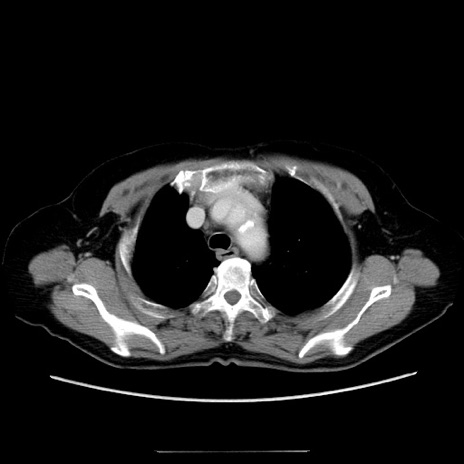

冠状断像

【症例】70歳代女性

【主訴】お腹が張る

【現病歴】1週間くらい前から腹部膨満の自覚あり。昨日夜から増悪したため、本日救急外来受診。

【身体所見】意識清明、BT 36.5℃、BP 165/106mmHg、HR 80bpm、SpO2 98%、腹部:膨満、軟、自発痛・圧痛なし、触診にて不快感あり、腸蠕動音:減弱

【データ】WBC 12600、CRP 1.04